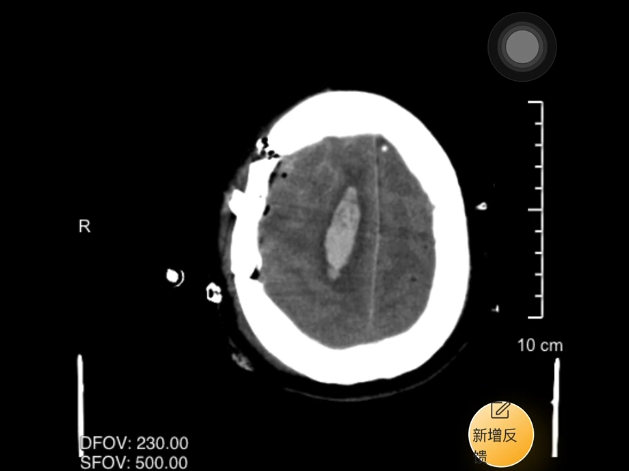

2025 年 3 月,56 岁的王女士因突发意识丧失就诊于三甲医院完善检查提示脑出血(右基底节区出血量高达 80 ml)在三甲医院行「颅内血肿清除」手术治疗后 2 周患者意识水平无改善,结合颅内出血情况专科考虑遗留「植物人」可能性大,被紧急送入南京健华康复医院五病区。80 ml 的出血量意味着极高的致残率与死亡率。